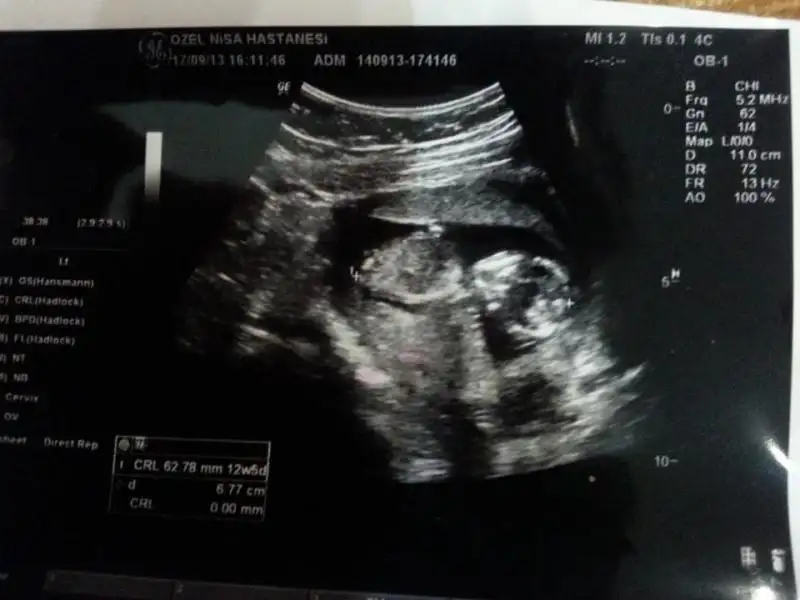

12+4 ultrason görüntüsü Eki Görüntüle 809800